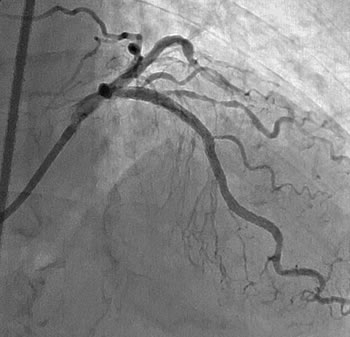

上左図の矢印部はまだ造影剤が注入されていないにもかかわらず、血管に沿って黒く見える部分があり、これが石灰化の存在を示しています。上右図において、その石灰化の部位に狭窄が存在しています。拡張不良が予想される所見です。

左冠動脈を正面上方より見る

最終的に、良好な拡張が得られました。また、理論上は細かく粉砕された病変は血管に詰まることはないはずなのですが、必ずしもそううまくはいかず、胸痛が長く続いたり、ひどい場合は心筋梗塞になってしまうこともあります。ですから、心筋梗塞を繰り返したために残された心臓の機能の少ない人や、著しく病変が長いために削られる病変の量が多いと予想される病変には、ロータブレーターによる治療はあまり適していません。ロータブレーターは基本的にプラーク表面付近の硬い組織を削り取る道具であり、その後、バルーンカテーテルおよびステント留置が行われます。